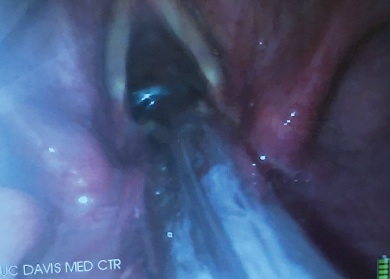

It is highly desirable to combine the use of the VL together with the FIS in this situation. Conventional FIS intubation is really a form of blind intubation. Even though the camera at the tip of the FIS confirms the tracheal position of the tip of the FIS there is no visualization of the vocal cords as the ETT is passing through them. When the airway is very anterior it is not uncommon to have a holdup of the ETT as it is attempted to be passed through the vocal cords. The potential for vocal cord trauma during this maneuver is very significant. Looking at the vocal cords with the VL as the ETT passes over the FIS will identify any damage that is occurring to the vocal cords. It also identifies the cause of any holdup that may be occurring. The VL view may also be used to identify maneuvers that may aid in getting the ETT to pass through the cords. Looking at the vocal cords during FIS intubation will make it obvious if the ETT is sufficiently aligned with the trachea and if anterior neck pressure should be applied to help guide the ETT into place. With this set up the intubator gets visual feedback about what effect manipulating the top of the ETT has at its distal tip. A common cause for failure of the ETT to slide over the FIS into the trachea is that the bevel of the ETT is impinging on the right arytenoid. In this situation pulling the ETT back 1 cm and turning the ETT 90 degrees to the left prior to advancing it again will allow the ETT to pass into the larynx. This 90-degree turning maneuver to the left allows the bevel of the ETT to clear the right arytenoid as it is pushed centrally between the cords against the FIS (Figure 6).

Figure 6: Video-laryngoscope (VL) view of the bevel of the endotracheal tube (ETT) impinging on the right arytenoid as it is attempted to pass it over the FIS into the trachea.

Pulling the ETT back one centimeter and turning it to the left will allow it to successfully clear the arytenoid and pass into the trachea. The use of the VL allowed the anesthesiologist to diagnose the cause of the holdup and prevented potential laryngeal damage. Turning the ETT 90 degrees to the left is a well known technique to prevent impingement of the ETT on the laryngeal inlet [39]. Another cause for holdup is the blind loop syndrome when the ETT pulls the FIS out of the trachea to form a blind loop. This usually occurs when the diameter of the FIS is too small for the diameter of the ETT. Again, this is readily diagnosed by looking at the cords with the VL. Occasionally, the ETT will not pass because the diameter of the ETT is too large for the patient's larynx. All of these causes of failure to successfully slide the ETT over the FIS into the trachea can be readily identified by the view obtained with the VL. The combined use of the VL together with the FIS is therefore preferable over the use of the FIS on its own. It greatly reduces the potential for airway trauma. It also allows the visualization of the ETT cuff just below the vocal cords and avoids inadvertent endo-bronchial intubation. This is a great advantage over standard DL when the cords cannot be visualized because following a difficult intubation the ETT is often inadvertently advanced into the right main bronchus. After a difficult struggle to insert the ETT into the trachea the anesthesia care provider wants to make sure the ETT does not accidentally get dislodged out of the trachea. In an attempt to prevent this the ETT is often advanced too far resulting in an endobronchial intubation. The poor view of the larynx with DL did not allow the cuff to be visualized just distal to the vocal cords. VL is helpful here because the cuff of the ETT can be seen just distal to the vocal cords (Figure 7).